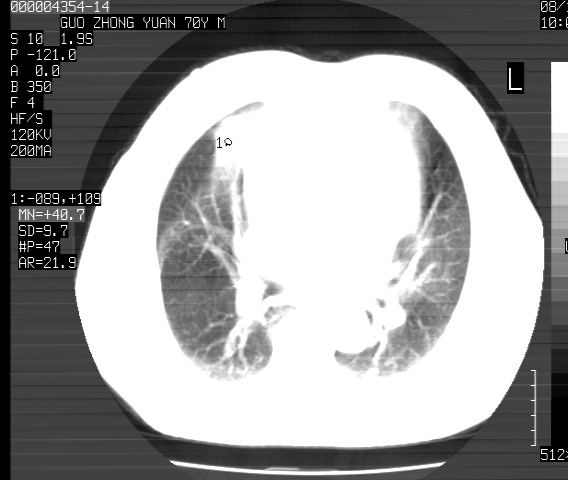

以下是引用sdzyy在2008-12-1 11:49:00的发言:[br]图像不全,请上传,右下肺炎症可能性大,占位待排.

以下是引用zjzjr在2008-12-1 14:53:00的发言:[br]图像不全,请上传,右下肺炎症可能性大,占位待排.心影增大,建议进一步检查.